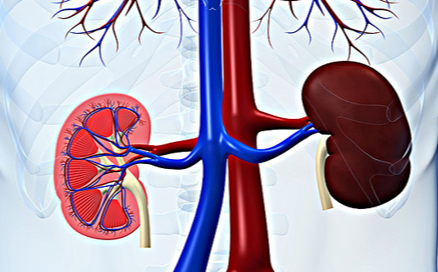

肾癌晚期很容易发生转移,肾癌转移的主要部位是肺和骨骼,其中骨转移站所有转移患者的20%-25%,而肾癌死亡患者尸检报告中发现骨转移率竟然高达40%,即使早期诊断并手术治疗的肾癌患者仍会出现一定比例的转移现象。肾癌骨转移容易侵犯脊柱、骨盆和四肢近端骨骼等部位,肾癌骨转移的治疗目的是去除病灶、缓解患者的疼痛、预防发生病理性骨折和截瘫、延长患者的生存期、提高患者的生活质量。